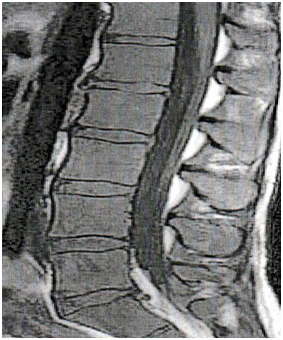

The standard MR protocol of the spine included sagittal T1-weighted and T2-weighted fast spin echo. Volume measurements are made by using a transparent template to overlay a grid of regularly spaced points over MRI scans of randomly selected patients (Figure 1). This point is counted as the full contact of the counter. Counts are made three times. The double or middle number is used. The volume of an object appearing on a scan (V) is the product of the sum of points that fell on the object, the area associated with each point (ap), and the distance between scan slices (t) in cubic centimetres.

Figure 1 Estimation of the volumes of lumbar intervertebral discs (a) using the Cavalieri method. A transparent square test grid system (2 mm) was superimposed on lumbar discs (b).